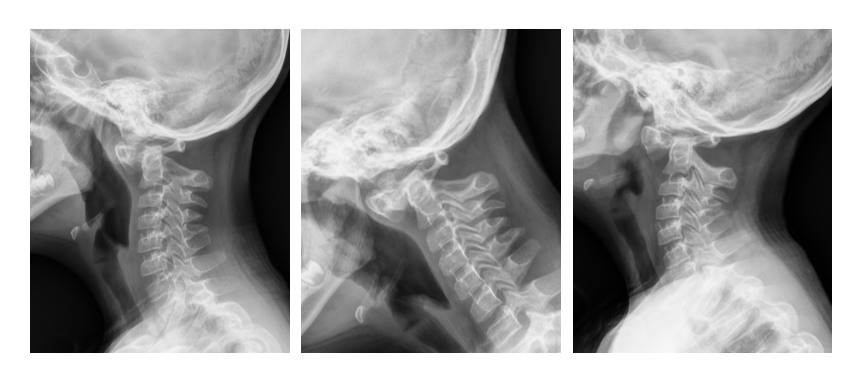

阳光讯(记者 郑亚雷 通讯员 黄王利)近日,西安市红会医院脊柱病医院许正伟主任的诊室,迎来了一位特殊的小患者——8岁的唐氏综合征患儿康康(化名)。康康母亲满脸焦虑:孩子最近总是拿手抱着脖子,玩耍时也小心翼翼。经详细检查,一个隐藏在颈椎最深处的危险被揭示:寰枢椎完全脱位。这如同在生命中枢的“枢纽”上发生了致命偏移,随时可能压迫脊髓,导致瘫痪乃至呼吸心跳骤停。

面对挑战,许正伟主任团队在西安市红会医院脊柱病医院院长闫亮、学科带头人贺宝荣主任带领下,为康康制定了周密的个性化方案。术前,三维椎动脉CTA精准“测绘”出脱位的详情与椎动脉的走向。由于患儿无法配合常规牵引,团队决定在术中实施高难度的颅骨牵引复位。